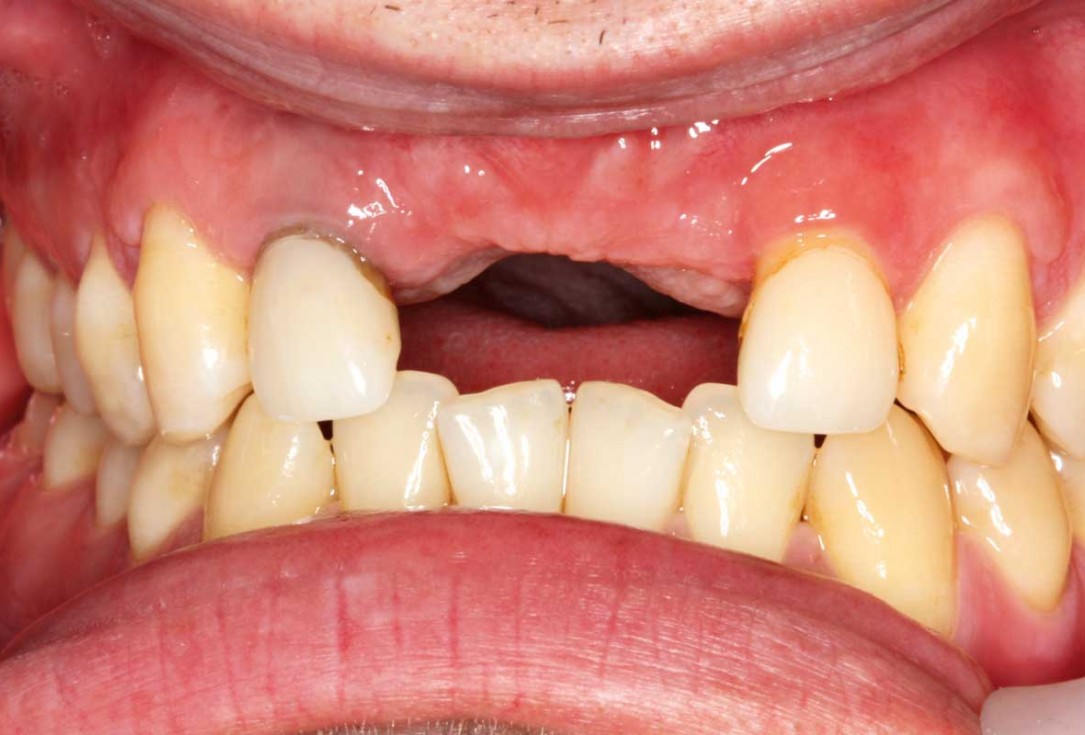

01/26 - Bone defect in area 11-21 due to two lost implants (periimplantitis) after 15 years of function